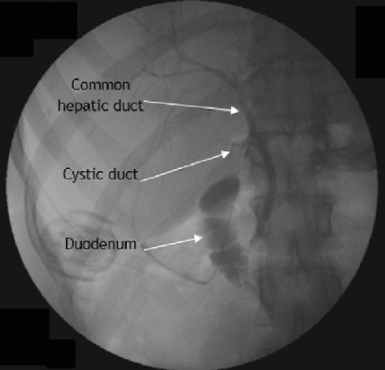

CPRE

• Colangiopancreatografía retrógrada endoscópica

• Introduce endoscopio con cámara hasta segunda porción de duodeno, después guía metálica a ciegas hasta usar canastilla y sacar lito

• Riesgo de pancreatitis: puedes ir a ducto pancreático, monitoriza 24h post

¿Para qué se hace colangiografía transoperatoria?

• Ver presencia de litos en vía biliar después de quitar vesícula

• Asegura que no quedaron litos y se hace transoperatorio

Colangioresonancia

* Goldstandard para visualizar vía biliar *** En caso de sospecha de lesión postoperatoria por patrón colestásico** * Ves si se ligó accidentalmente conducto**colédoco o hepático común,** * Si si en la imagen no pasaría contraste